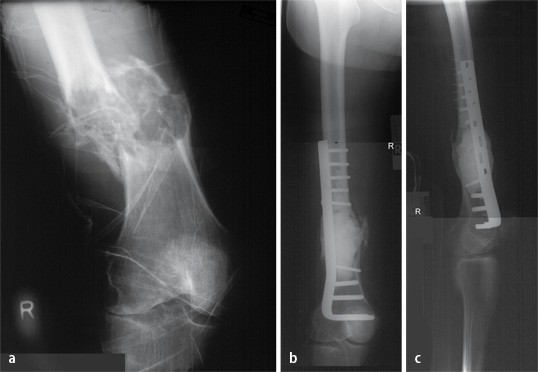

Effiziente Diagnostik Pathologischer Frakturen Sciencedirect

Periprosthetic Tibial Fractures In Total Knee Arthroplasty An Outcome Analysis Of A Challenging And Underreported Surgical Issue Bmc Musculoskeletal Disorders Full Text